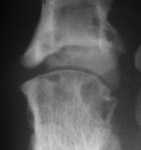

Gout: Large erosions 5th MTP joint

++